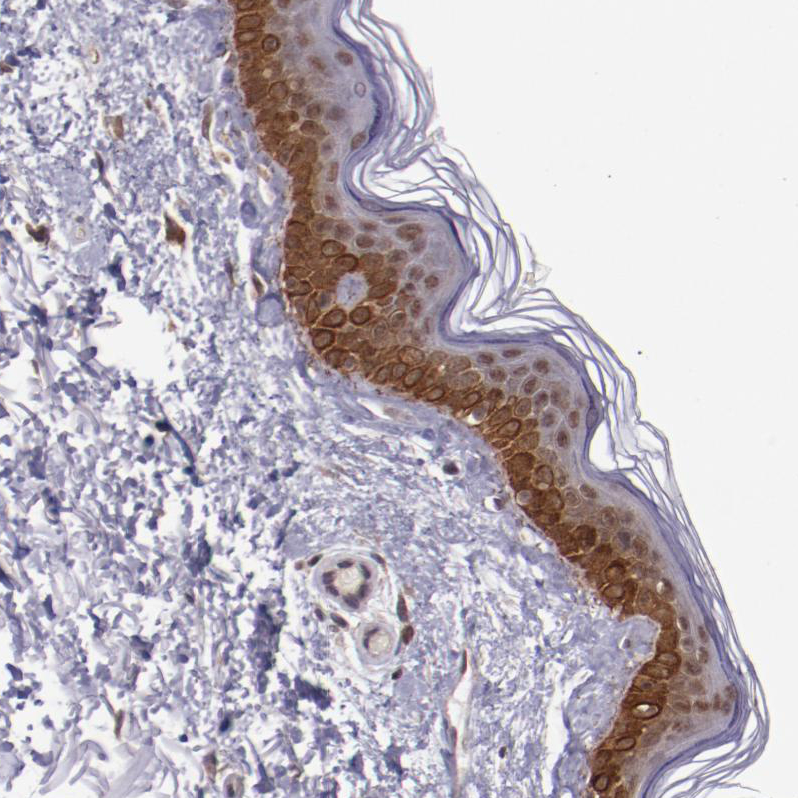

Immunohistochemistry analysis in human lymph node and skeletal muscle tissues using HPA001755 antibody. Corresponding ELF1 RNA-seq data are presented for the same tissues.